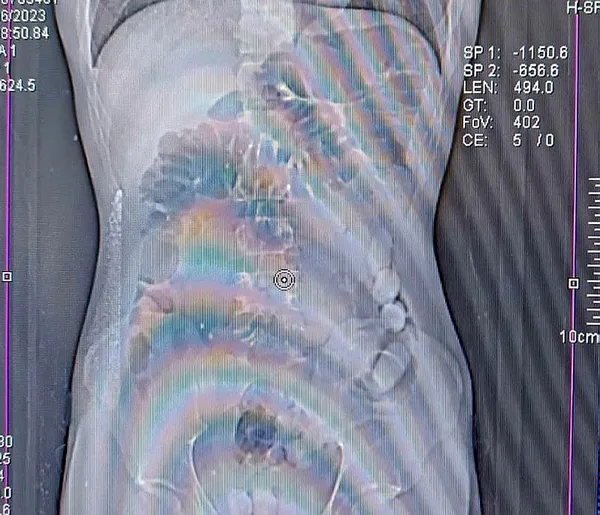

Bu çerçevede durdurulan yolcu otobüsünde, yutma yöntemiyle uyuşturucu taşıdığı değerlendirilen İran uyruklu M.M.A ve O.A gözaltına alındı. Şüphelilerin mide ve bağırsaklarında yapılan tomografi çekimlerinde çok sayıda yabancı cisim bulunduğu tespit edildi.

Yapılan tıbbi müdahale ile M.M.A'nın midesinden çıkarılan 81 adet 934,96 gram ile O.A'nın midesinden çıkarılan 67 adet 813,07 gram afyon sakızına el konuldu.